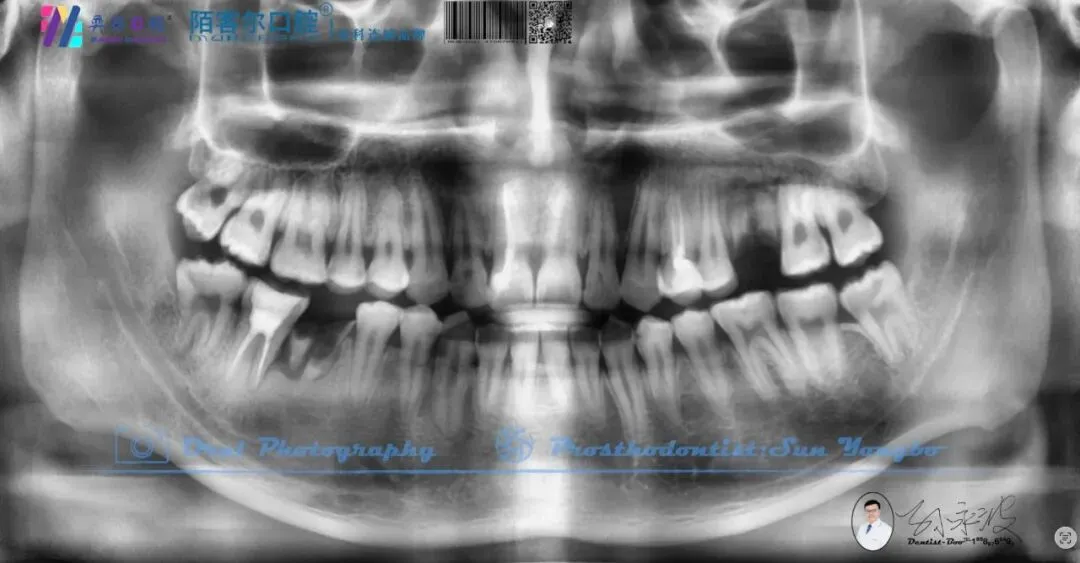

【深圳牙医-孙永波】病例16丨右下后牙单颗缺失种植修复